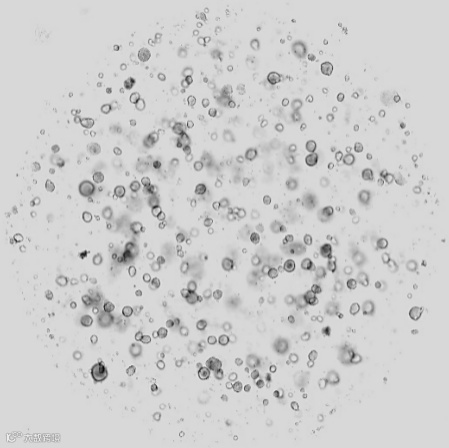

肺腺癌类器官原代培养(Day0)

深圳市李老师使用SmartOrgan Dissociator测试了肺腺癌组织样本,细胞活性均≥90%,细胞得率在1- 5*104 cells/mg。

我们使用智能组织解离系统测试了3例肺腺癌样本,最终我们得到的细胞活性分别为94.44%、95.16%、92.21%,细胞得率分别为2.89*104 cells/mg、1.71*104 cells/mg、5.19*104 cells/mg,这个结果符合我们的实验严要求,也为我们后续的实验提供了优质的起始材料。仪器操作十分简单,解离运行时间仅约10分钟,我对伯桢生物的这款设备充满期待,它不仅提升了我们实验的效率,更重要的是,它确保了实验结果的高活性和高得率,这对于科研的稳定性和可重复性至关重要。我期待伯桢生物能够持续其创新精神,不断推出更多高质量的科研仪器,与我们一同推动生物医学研究的前进步伐。